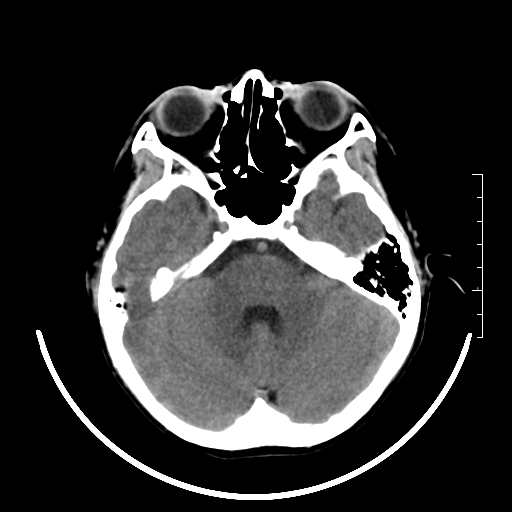

标题: PED3377:m、9y,恶心、呕吐,每月发作2-3次。 [打印本页]

标题: PED3377:m、9y,恶心、呕吐,每月发作2-3次。

右侧基底节区见钙化灶

右侧壳核多枚点状钙化灶。去请结合临床。

右侧壳核多枚点状钙化灶,请结合临床。

右侧壳核多发钙化灶,请结合临床。

桥前池是不是有点大?